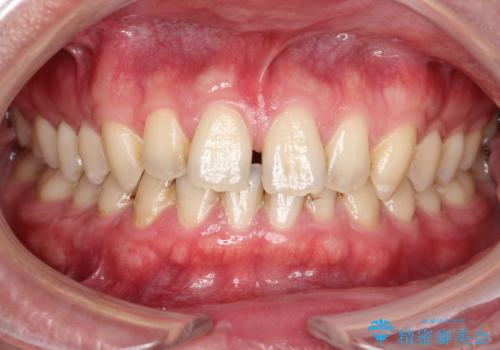

[ インビザラインライト ] 14枚で行う前歯のみの短期間マウスピース矯正

担当医 大元洋佑